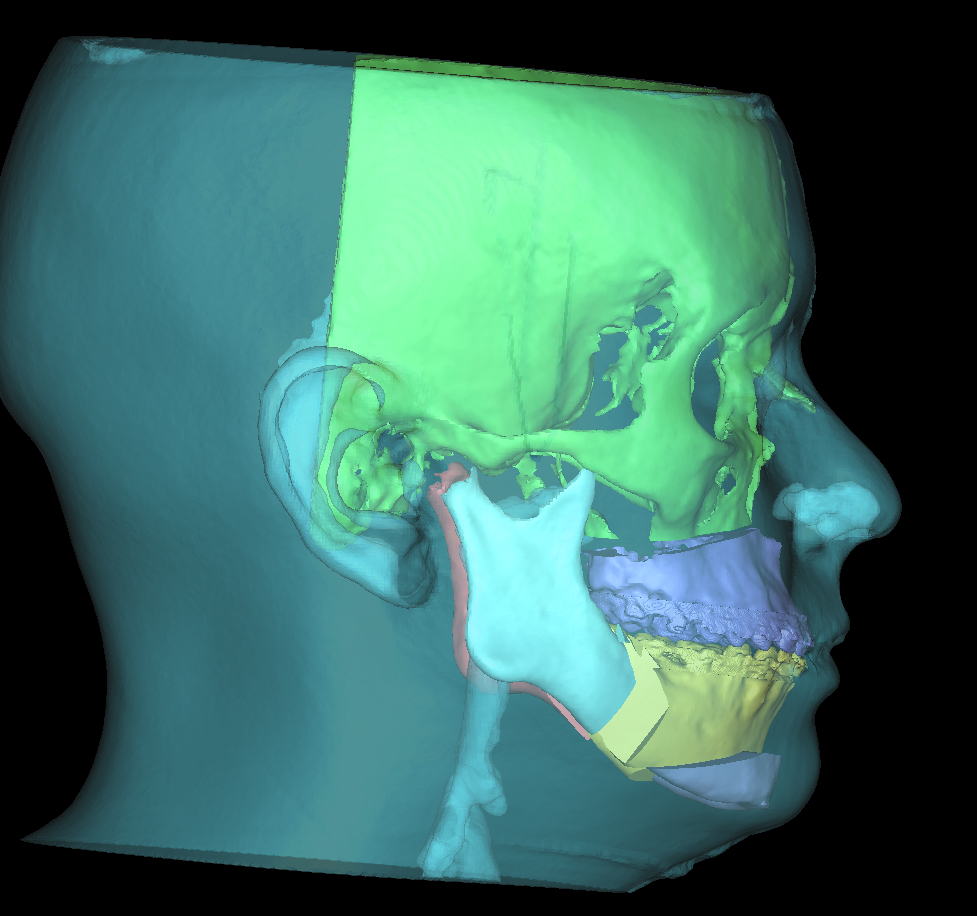

Als de orthodontische voorbereiding voor de operatie ver gevorderd is, wordt de kaakoperatie door de kaakchirurgen digitaal gepland in 3D.

Met een prachtig digitaal planningsprogramma in samenwerking met het UMCG, wordt bepaald wat het mooiste resultaat geeft. Hieronder geven we voorbeelden van hoe zo’n planning er uit kan zien. In dit voorbeeld wordt de bovenkaak verplaatst, de onderkaak en de kin. Vaak kan de operatie ook beperkt worden tot alleen een onderkaak of alleen een bovenkaak. Het is maar net wat per specifiek geval de beste oplossing is.

en het effect daarvan op de ‘weke delen’ zoals lippen en kin en profiel.

Nu kan dee kaakchirurg goed voorbereid de operatie plannen.